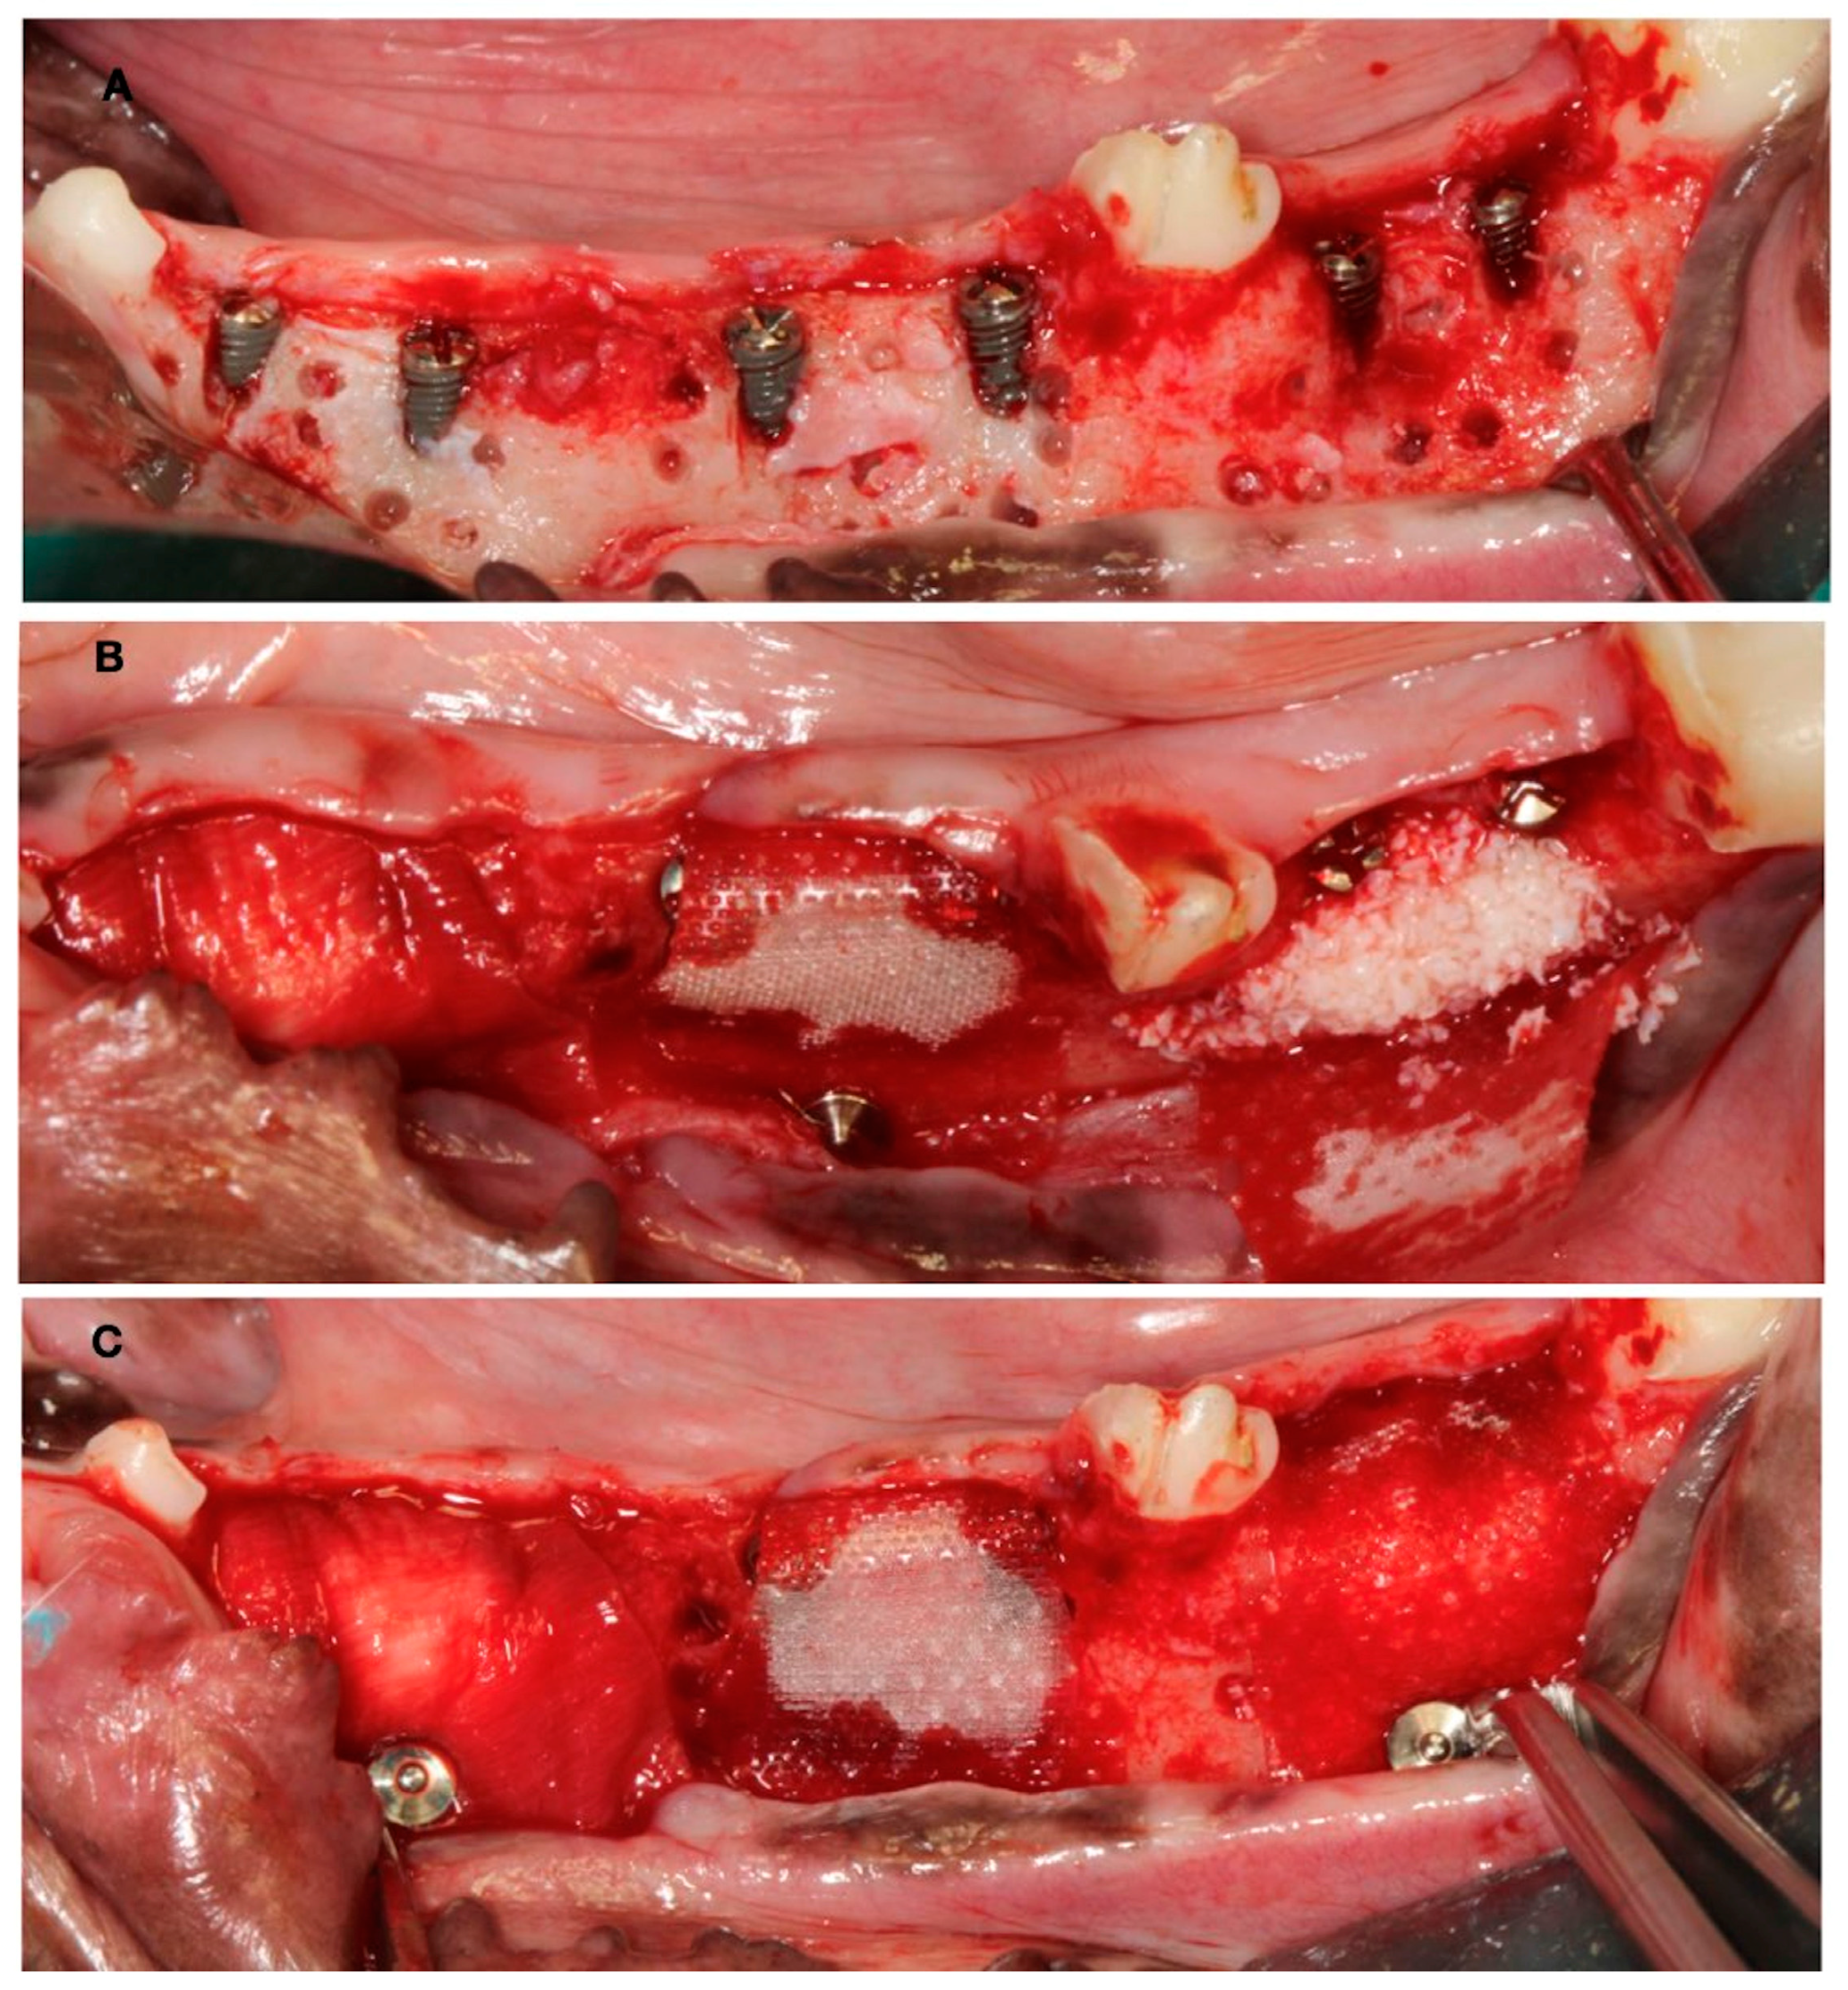

2.2. Surgical Interventions

- The test group using deproteinized bovine bone mineral (DBBM) (BioOss®, Geistlich Pharma, Wolhusen, Switzerland) combined with a synthetic polylactic membrane (PLAB) (GUIDOR®, Sunstar, Schlieren, Switzerland)

- The positive control group using DBBM (BioOss®, Geistlich Pharma, Wolhusen, Switzerland) combined with a natural porcine collagen membrane (NPCM) (BioGide®, Geistlich Pharma, Wolhusen, Switzerland)

- The negative control group using only the synthetic polylactic membrane (PLAB) (GUIDOR®, Sunstar, Schlieren, Switzerland)